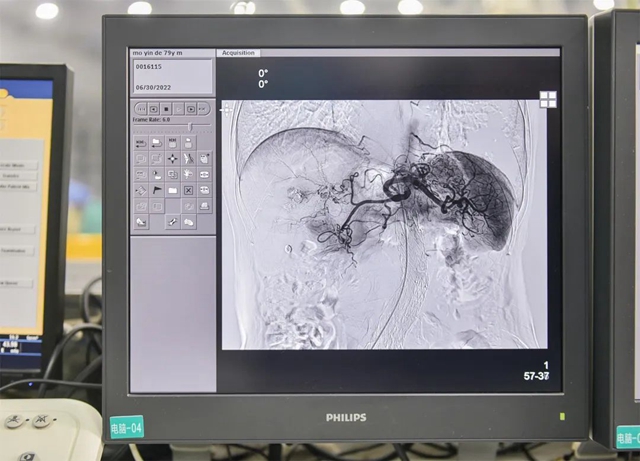

6月30日,在西南医科大学附属医院的介入手术室内,随着钇-90微球注射液缓缓注入到患者体内,全国首批、西南地区首例钇-90微球注射治疗肝癌手术成功完成。标志着西南医科大学附属医院在肝脏恶性肿瘤综合治疗能力上了一个新台阶,为西南地区乃至全国的肝脏肿瘤患者带来全新的治疗模式和生命的希望。

西南医科大学附属医院肝胆外科主任李波教授介绍,肝癌被称为“癌症之王”,起病隐匿,多数患者发现时已是中晚期。此次接受治疗患者是79岁的老年男性患者,2015年发现的肝癌,经历了多次手术切除、介入栓塞治疗、消融治疗等治疗手段。2个月前肿瘤再次复发,而且位置在肝脏的边缘位置,手术难度很大、风险也很高。现在通过介入手术,让钇-90微球直接作用在病灶,持续发挥作用,有针对性的杀死肿瘤细胞,避免了手术创伤,提高了安全性。